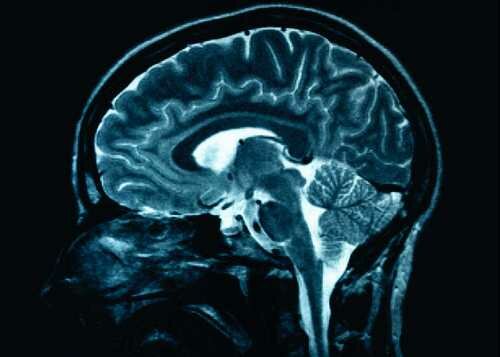

If you want to know the system of human mind, you need to read Facts about The Mind. All mental processes and psychic activities in an organized system are called as the mind. The detector of the mind is in our brain. There are many scientists and philosophers who want to describe and define the mind since the ancient era. Here are facts about human mind for you:

The mind often forgets something because two purposes. The first one is used to avoid the emotional hangovers. The second one is used to avoid the overload information in the brain. It is okay for you to forget something. Get facts about brain here.